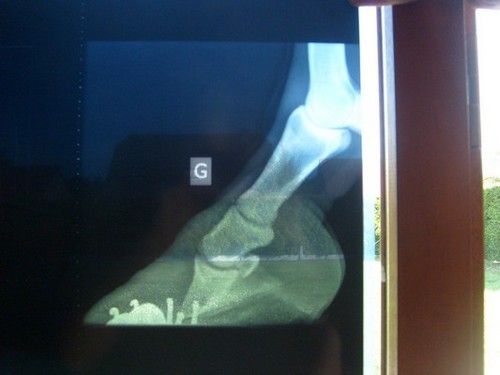

| Dire merci | Bonsoir, je sais qu'il existe déjà plusieurs post au sujet de la fourbure, mais je voudrais avoir des témoignages de personnes qui ont ou ont eu des poneys ou chevaux fourbus, et savoir comment cela à évoluer. J'ai achetée il y a 8mois, une ponette croisée Fjord de 11ans fourbue, Quand je l'ai eue, elle restée couché trés souvent d'après ses anciens proprios (qui malheuresment ne connaissait rien a la fourbure). Après un premier parage, kétie restée debout toute la journée, vient ensuite 3mois après une boiterie à l'antérieur gauche, qui vient et repart comme ça, on fait des radios voilà ce que sa donne ![]() Je change de maréchal sur avis véto car il n'a pas du tout adapté son ferrage (pince trois fois trop longue, fers de postérieurs, talons trop longs, et a perçé une partie molle de la sole croyant que c'était un abcès )Depuis kétie a des fers à l'envers avec plaques en cuir, elle revit depuis, mais "marque" toujours au trot. Je la change de pension pour qu'elle puisse marcher le plus possible. Une photo de ma belle courageuse ![]() Je ne sais plus quoi faire a part attendre de voir si elle ne marque plus, autant vous dire que l'avis du véto n'est pas optimiste, même si je vois des améliorations depuis quelques mois. et vous qu'avez vous fait ? |

j'ai connu une fjord rachetée par une amie in extremis, le véto disait qu'elle s'en sortirait pas, elle ne se levait plus du tout, mais quand je l'ai connue elle remarchait très bien et était montée régulièrement en balade ![]() elle a eu chaud, mais s'en est bien sortie. par contre je ne saurais pas te dire exactement quel traitement a été fait, ni quelle ferrure. quand je l'ai connue elle avait une ferrure tout a fait normale, le seul truc c'est qu'elle était au régime toute l'année. d'après les radios il y a bascule de la phalange, c'est donc une fourbure chronique, après la ferrure qu'elle a actuellement c'est cohérent avec son problème ![]() je laisse ceux qui ont vécu la même chose répondre ![]() |